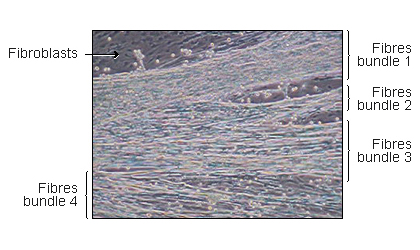

Muscle fibers

4 innervated fibers muscle bundles

on muscle derived cells monolayer -

Myoblasts and Fibroblasts

Muscle derived cells, mainly myoblastes and fibroblasts are cultured in monolayers. Immediately after myoblaste fusion, whole transverse slices rat embryos spinal cords with dorsal root ganglia attached are placed on the muscle monolayer. After 24h neuritis are observed growing out of the spinal cord explants. They make contacts with myotubes and induce the first contractions. Quickly thereafter, innervated muscle fibres located in proximity to the spinal cord explants, are virtually continuously contracting (see movies on our website). Innervated fibres are morphologically and spatially distinct from the non-innervated ones and could easily be distinguished from them

(Askanas et al., 1987) .